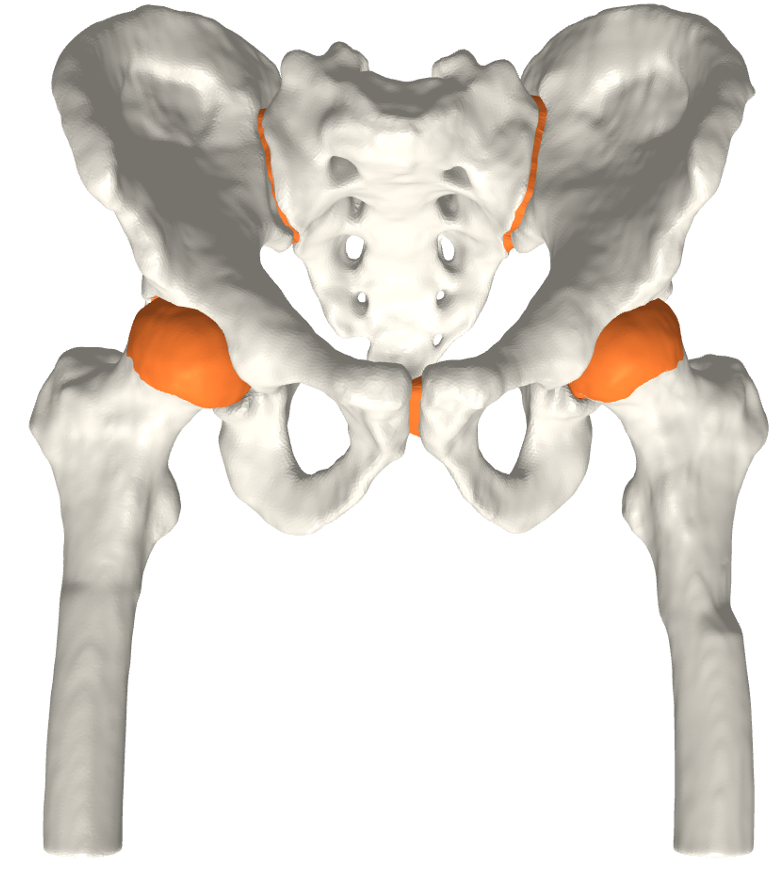

We have qualitatively verified that the articulating surfaces in all the ten HJs are detected correctly regardless of their anatomical variance using visual inspection of overlays as shown in Fig. 4. As desired, we observe a high degree of congruence between the opposing joint surfaces, meaning no gaps or overlaps in the cartilage-cartilage interface. Moreover, we observe a smooth transition towards the bone geometries as expected from the correct anatomy. The parameter values used to generate the cartilage from Fig. 5(a). The free parameters are the neighbourhood-size used to estimate the curvature of the bone (𝒩𝒩\mathcal{N}); the minimum and maximum curvature in the cartilage region (κmin,κmaxsubscript𝜅subscript𝜅\kappa_{\min},\kappa_{\max}; Eq. (2)); the distance parameter in mm𝑚𝑚mm (δ𝛿\delta; Eq. 1); and the number of times the outer boundary should be trimmed (Ntrimsubscript𝑁𝑡𝑟𝑖𝑚N_{trim}). Here, the curvature based parameters (𝒩,κmin,κmax)\mathcal{N},\kappa_{\min},\kappa_{\max}) are only used for the femur. See supplementary material for more visual comparisons.

Fig. 4 visualizes the von Mises stress pattern on the pelvic cartilage for one HJ. More are shown in the supplementary material. We have verified that no spurious stress peaks appear and that stress values change gradually and smoothly across the cartilage. Further, the high-stress areas are located in the up-direction, as we expect from the applied displacements. The stress values and patterns are not to be confused with those from a real stance. They only serve as a verification test of simulation properties. For such a simulation, we require ligaments and muscles to stabilize the girdle and a correction from sublime pose bias.

(b) CT scan overlay.

Figure 4: The von Mises stress patterns ((a)) and the generated cartilage imposed on the CT scan from which the bone was extracted ((b)). Notice the high level of congruence in the cartilage-bone interfaces and cartilage-cartilage interface.